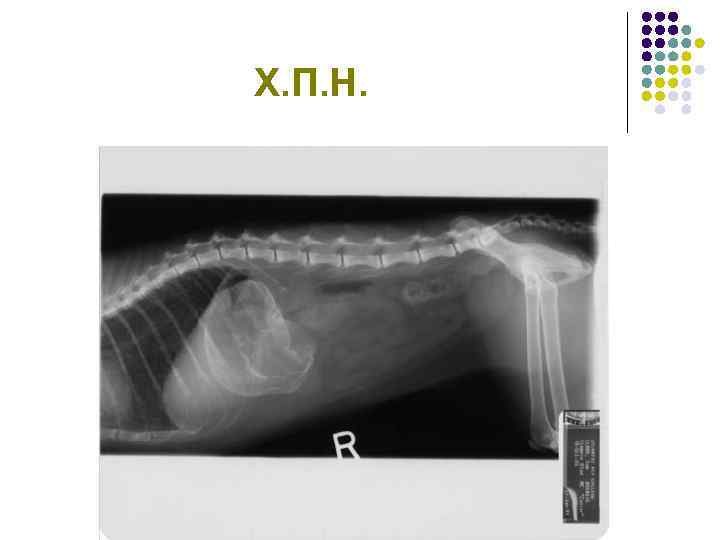

Х. П. Н.